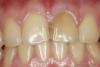

an_ver Опубликовано 2 мая, 2013 Поделиться Опубликовано 2 мая, 2013 Сколы по режущему краю 11,21.Изменение цвета 21.Задача поставлена: цвет 11,21 должен быть однотонный, выравнивание режущих краев, удлинение.Сделали вакс ап, примерили,дали привыкнуть.Немного укоротили,стало гуд.Еще походила,все хорошо.Препарировал,слепки,временные виниры,фиксация на темп бонд.Вопрос: кто как временные виниры фиксирует...слетают Ссылка на комментарий